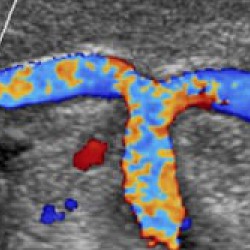

• Функция Auto Doppler автоматизирует рутинные действия, связанные с исследованием сосудов. Она улучшает шкалу серого, автоматические параметры допплеровского режима, корректирует углы и цвет.

Трехмерная реконструкция ЦДК:

Да

Цветовой допплер:

• Цветной допплер (CD) - Да

• Энергетический допплер - Да

• Опция получения трехмерного изображения в режиме цветового допплеровского картирования (трехмерная реконструкция ЦДК) - Да

• Опция получения трехмерного изображения в режиме цветового допплеровского картирования - Да